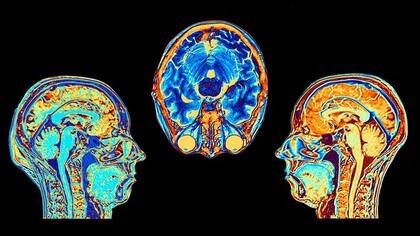

Los especialistas descubrieron que hay diferentes tipos de estimulación cerebral que pueden ayudar a determinar y mejorar la calidad del descanso

Un creciente conocimiento de esta vía neuronal está llevando a algunos científicos a investigar si diferentes tipos de estimulación cerebral pueden calmar el punto azul para mejorar el sueño. Un equipo de Corea del Sur, por ejemplo, probó recientemente un auricular que hace pasar una pequeña corriente eléctrica por uno de los nervios de la frente que está conectado al punto azul para amortiguar temporalmente su actividad, aunque todavía no se sabe si esto reduce el insomnio.